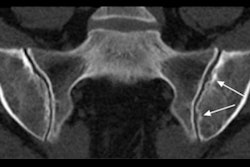

MR images are from a 17-year-old girl with polyarticular rheumatoid juvenile idiopathic arthritis and mild synovial inflammation. The score from the DWI dataset agreed with the reference standard that arthritis was present in this knee. Arrows indicate areas of synovial inflammation. ADC = apparent diffusion coefficient. Images courtesy of Radiology.When the researchers compared synovial inflammation detection between DWI contrast-enhanced MRI, regardless of the reference standard, the two approaches agreed in 37 of the cases (82%), resulting in a sensitivity of 92% and a specificity of 78%

MR images were anonymized and randomized and interpreted by two readers blinded to all clinical data. Their evaluations served as the reference standard in which they found arthritis in 14 children (31%) and no arthritis in 31 children (69%). Based on those diagnoses, DWI confirmed 13 of the 14 arthritis cases for a sensitivity of 93% and 25 cases with no arthritis for a specificity of 81%. Diagnostic confidence between the two readers had a median score of 99.